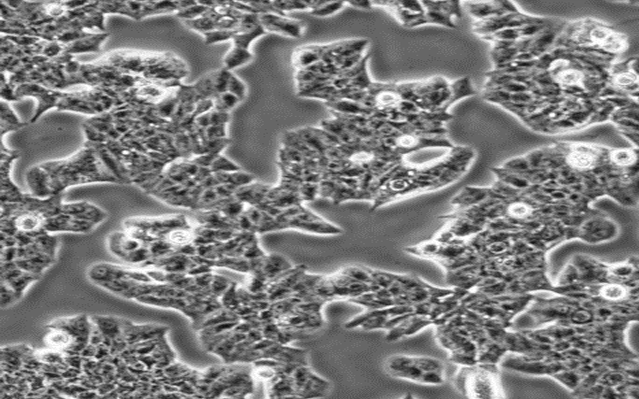

SJSA-1;人骨肉瘤细胞

D283 Med;人脑髓母细胞瘤细胞

MDA-MB-361;人乳腺癌细胞

H4;人神经胶质瘤细胞

SK-N-MC;人神经上皮瘤细胞

SK-N-AS;人脑神经母细胞瘤细胞

Daoy;人脑髓母细胞瘤细胞

DU4475;人乳腺上皮细胞

BT-20;人乳腺癌细胞

VIEW MORE